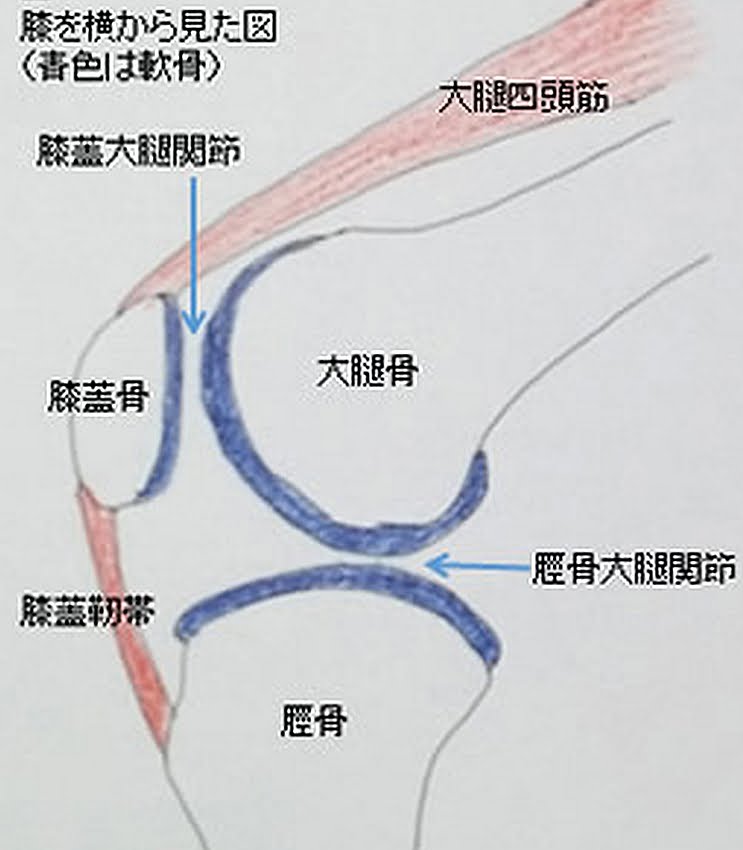

"皿"=膝蓋骨(しつがいこつ)以外の

自分の膝の箇所の骨が何処(半月?)か折れた

とも感じました。以下足の"膝部”の図解となります。

人間の膝というのは極めて複雑な組織で形成されています。